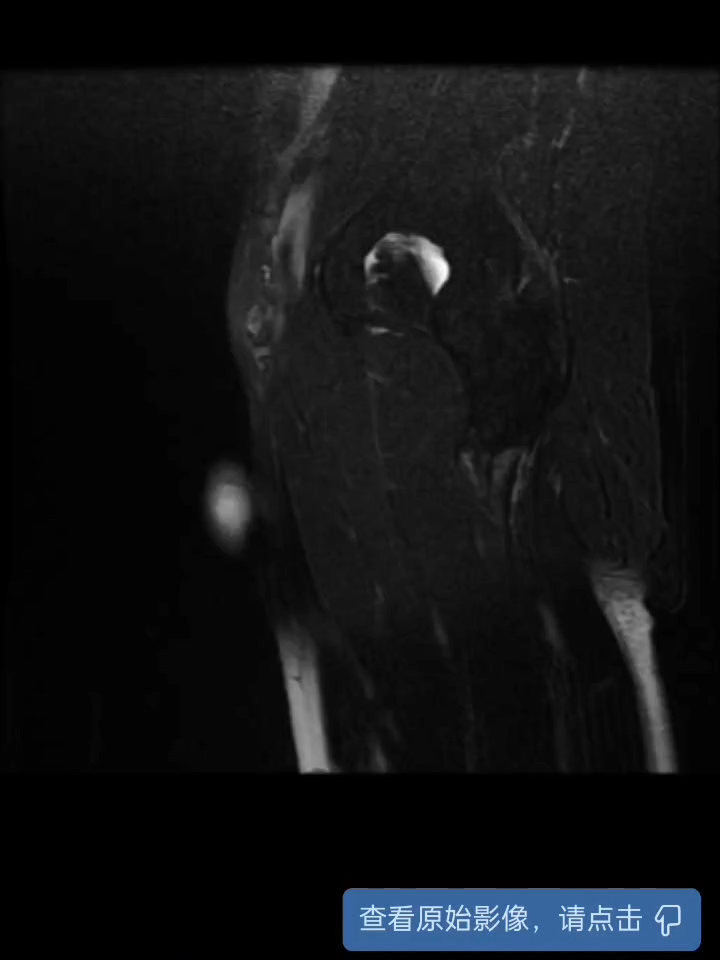

【治疗经过及结果】:完善睾丸及附睾彩超提示左侧睾丸、左侧附睾增大,左侧睾丸、左侧附睾实质回声不均质,考虑睾丸附睾炎可能,但不排除睾丸肿瘤可能,予进一步完善下腹部MRI了解病情;针对患者情况,予选用广谱抗生素,故予抗感染,止痛治疗。

磁共振结果: